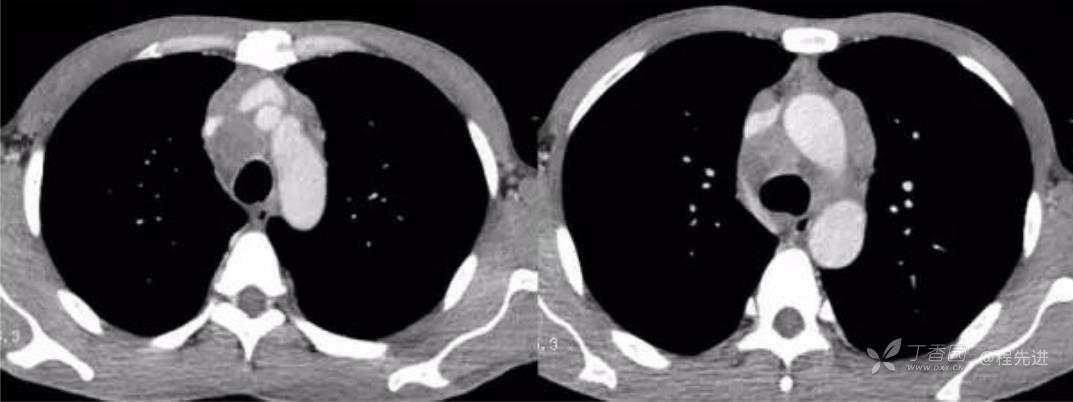

平扫纵隔窗

动脉期